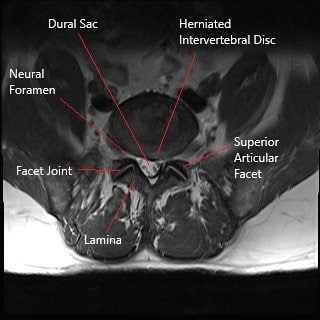

Los discos intervertebrales consisten en un centro gelatinoso blando (núcleo pulposo) que está contenido dentro de un anillo externo duro (anillo fibroso). Las grietas pueden aparecer en el anillo exterior debido a la enfermedad degenerativa del disco o debido a acciones repetitivas o traumatismos. El centro interno blando puede herniarse a través del anillo y conducir al adelgazamiento del anillo exterior. A veces, el núcleo puede ser extruido fuera del anillo exterior por completo.

La hernia de disco intervertebral crea inflamación local y comprime las raíces nerviosas espinales que salen o atraviesan. La compresión de las raíces nerviosas y el saco dural puede provocar síntomas de parestesia, dolor y debilidad en el área suministrada por la raíz nerviosa. El disco intervertebral es suministrado por los nervios sinovertebrales que surgen de las raíces nerviosas. Los nervios sinovertebrales se irritan como resultado de la hernia y conducen a dolor lumbar.

La hernia de disco intervertebral es diagnosticada clínicamente por el médico. El médico puede solicitar estudios radiológicos para una investigación adicional. Una radiografía le permite al médico ver la estructura ósea de la columna lumbar. La imagen de rayos X es capaz de mostrar cambios artríticos en la columna lumbar, cualquier fractura o cualquier estrechamiento del canal. La resonancia magnética es a menudo el estudio más útil para diagnosticar una hernia de disco. Las imágenes de resonancia magnética pueden mostrar todas las estructuras de tejidos blandos en la columna lumbar, incluidos los nervios.